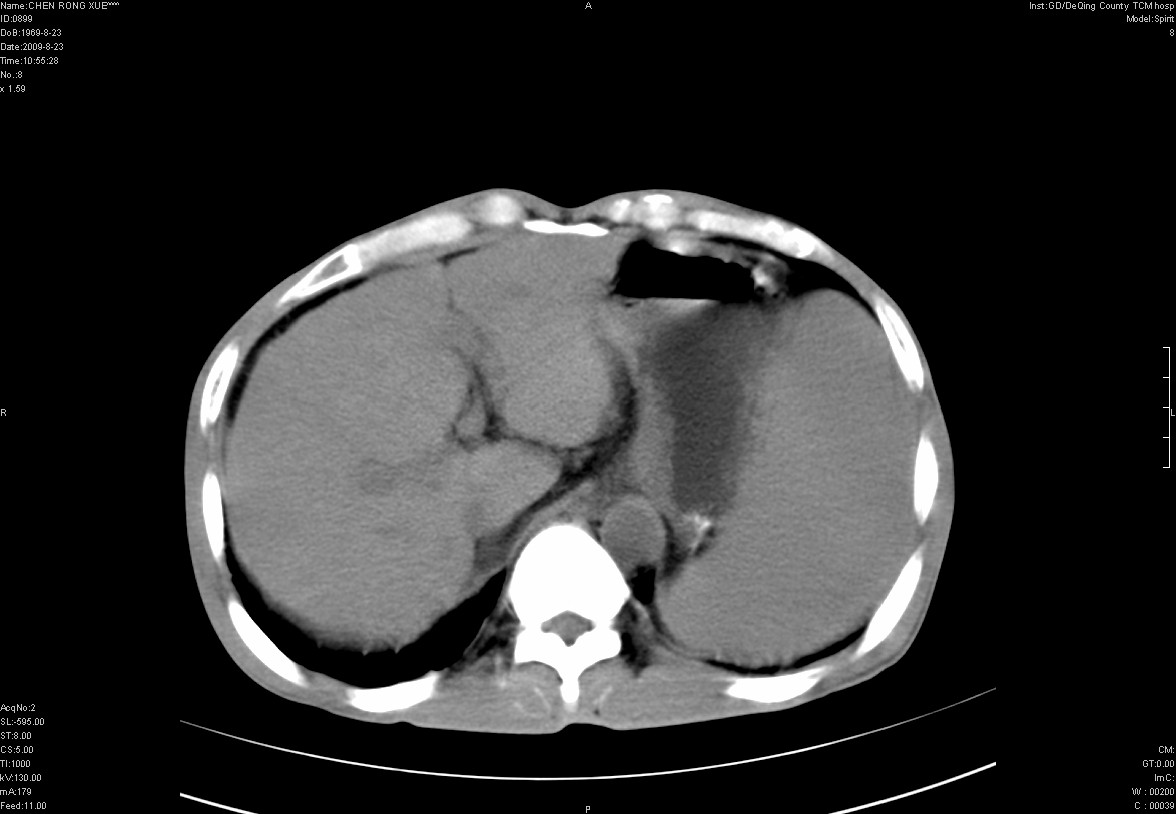

以下是引用zxl51642在2009-8-23 12:56:00的发言:[br]1、肝硬化、脾大;2、慢性胆囊炎;3、右肾占位并右侧腰大肌受侵,考虑恶性可能性大,建议增强扫描进一步检查。

以下是引用qiuleiyu在2009-8-23 15:17:00的发言:[br]1、慢性肝病,肝硬化,脾大,门脉高压。胆囊小结石。[br]2、右肾明显肿大,伴片状低密度灶,累及右侧腰大肌,肿瘤及炎症性病变皆有可能大,建议增强。

以下是引用zjzjr在2009-8-23 17:42:00的发言:[br]1、慢性肝病,肝硬化,脾大,门脉高压。胆囊小结石。[br]右肾脓肿波及肾周,建议增强

以下是引用dyqct在2009-8-23 16:53:00的发言:[br][quote]以下是引用qiuleiyu在2009-8-23 15:17:00的发言:[br]1、慢性肝病,肝硬化,脾大,门脉高压。胆囊小结石。[br]2、右肾明显肿大,伴片状低密度灶,累及右侧腰大肌,炎症性病变可能,建议增强。